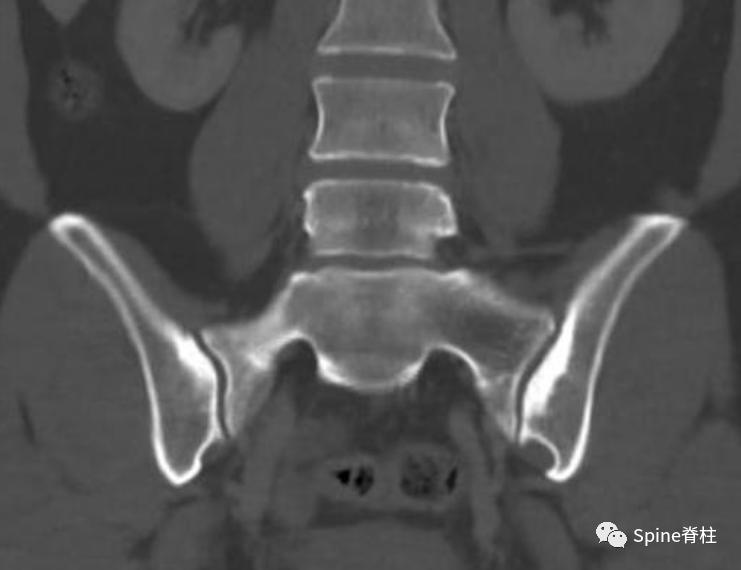

髂骨致密性骨炎通常是偶然诊断出来的。骶髂关节的髂侧表现出硬化,通常呈双侧、对称和三角形。硬化区轮廓分明且致密,主要位于关节的前中三分之一处。诊断主要依靠影像学上无骶骨受累和关节间隙变窄,但可能会出现骶骨附近对称性小局灶性硬化。此外,单侧髂骨致密性骨炎已有文献报道。

骶髂关节的髂侧硬化,无骶骨受累或关节间隙狭窄。图片来源:https://doi.org/10.53347/rID-12390

主要的鉴别诊断是骶髂关节炎或骶髂关节骨关节炎。对于髂骨致密性骨炎,骶髂关节是正常的,没有不规则、侵蚀或关节间隙的丢失。